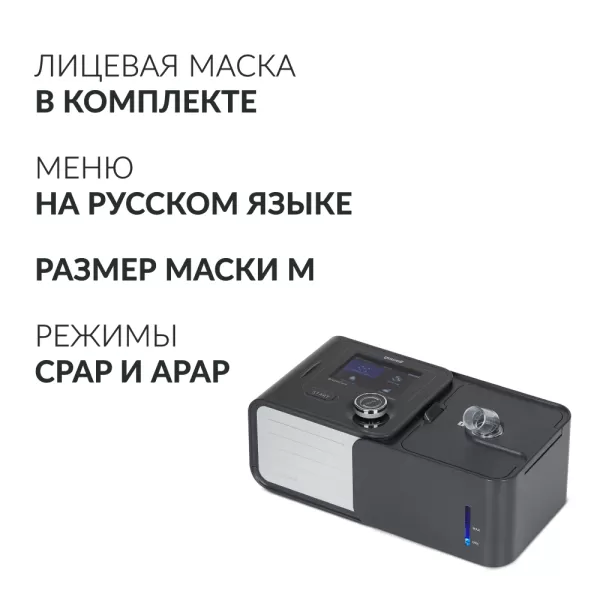

Арт.: 1954001

39 900 руб./шт

Под заказ

Арт.: 2033401

135 900 руб./шт